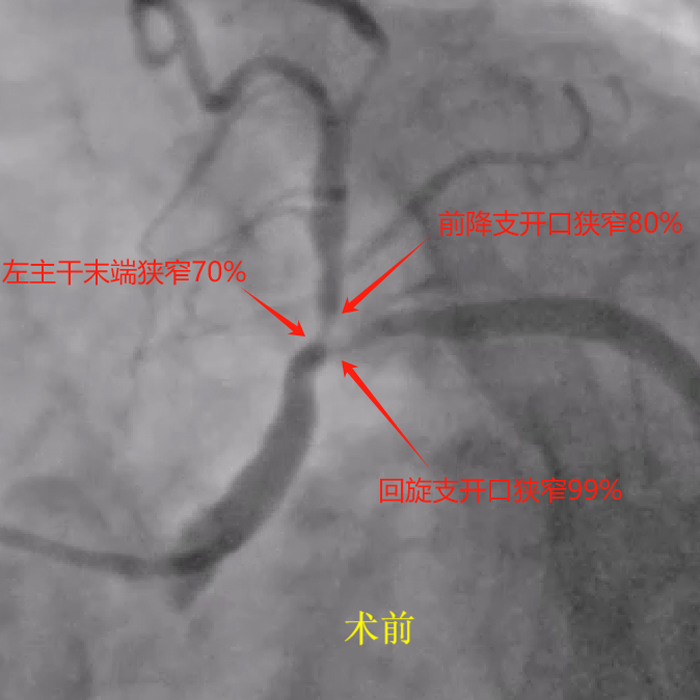

据了解,杨某,女性,85岁,因反复胸痛来到来凤县人民医院心血管内科就诊,诊断为冠心病 不稳定型心绞痛,心血管介入团队为患者行冠脉造影,造影提示患者左主干末端分叉病变,左主干末端狭窄70%,前降支开口狭窄80%,回旋支开口狭窄99%。

该患者85岁,但其左主干末端、前降支及回旋支开口病变严重,如不及时处理随时有猝死风险,需行左主干分叉病变支架植入术。而此植入术是介入手术中风险最高的一类手术,这对介入手术团队也是一个极大的挑战。